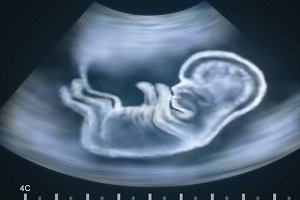

По словам психологов, решившаяся на аборт женщина пытается игнорировать мысли о том, что ее ребенок существует в действительности. Когда женщине показывают плод на экране аппарата УЗИ, ребенок предстает в ее глазах таким, какой он есть. Если женщина услышит сердцебиение, она будет знать, что даже через три недели после зачатия, у малыша уже бьется сердце.